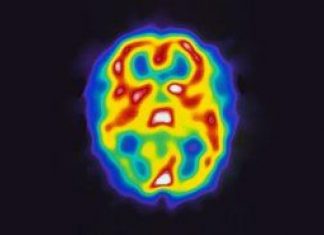

Study: New method to identify genes that can drive development of brain tumors

Researchers at Uppsala University have developed a method for identifying functional mutations and their effect on genes relevant to the development of glioblastoma -...